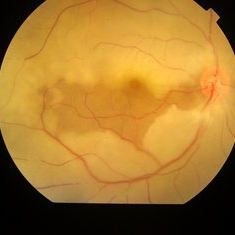

Branch Retinal Vein Occlusion with Macular Edema Branch Retinal Vein Occlusion with Macular EdemaDec 11 2022 by Anjana Mirajkar, MS Ophthalmology Central color photo of a 54 year old male case of LE Branch Retinal Vein Occlusion with Macular Edema. Photographer: Dr. Anjana Mirajkar -Retina Foundation, Ahmedabad. Condition/keywords: branch retinal vein occlusion (BRVO)